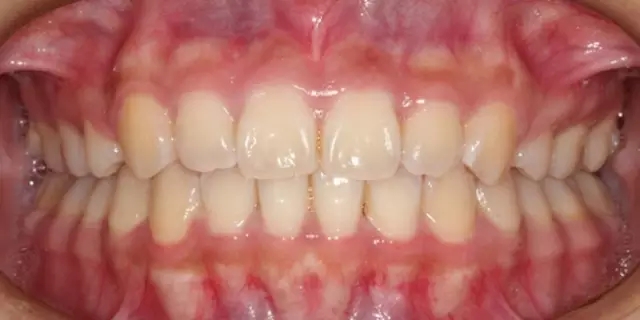

Damon 病例分享:安氏 II 類(lèi)二分類(lèi)露齦笑的矯治(董一磊)

治療前后對(duì)比